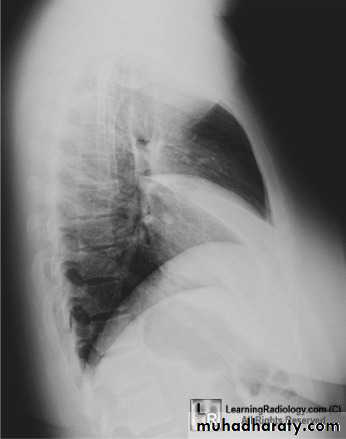

6.lateral film position

7.decubitus film

32.RT ML consolidation ( PA & lat. view )

33.RT ML consolidation (Lat. view )

34.LUL consolidation (PA & Lat. View )